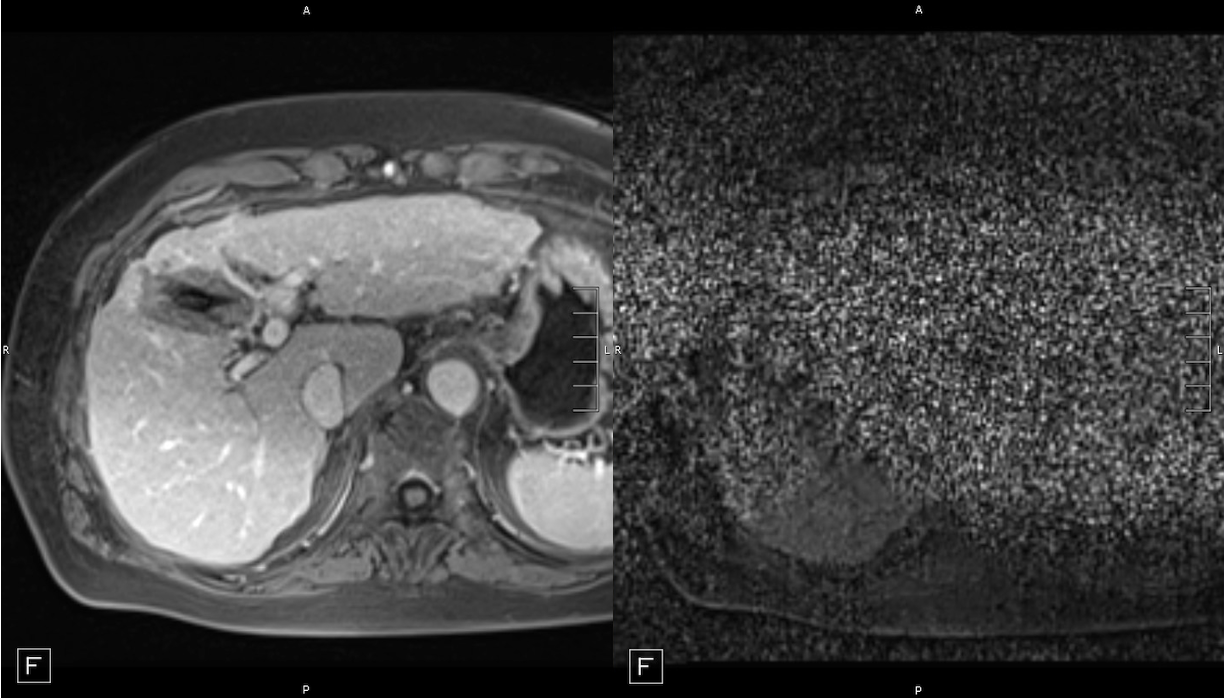

In the realm of real-time 3D thermometry, particularly during microwave ablation procedures, one significant challenge has been the electromagnetic interference (EMI) from the microwave generator. This interference couples with the MRI scanner, resulting in images that are marred by noise, making accurate and real-time 3D thermometry a complex task. The noise can significantly impede the clarity of images, thus affecting the precision and effectiveness of the treatment monitoring.

Addressing this critical issue, our research group has successfully implemented shielding measures for the microwave generator [4][5]. These measures are meticulously designed to mitigate EMI, ensuring that the noise in the MRI images is substantially reduced. By doing so, we have been able to maintain the integrity of the imaging process, allowing for clear and accurate real-time 3D thermometry even during the Microwave Ablation.

The implementation of these shielding techniques marks a pivotal advancement in the field. It enables clinicians to perform microwave ablations with greater confidence in the accuracy of the real-time 3D thermometry readings. This development not only enhances the safety and effectiveness of the procedure but also paves the way for broader applications of this technology in various clinical scenarios. The ability to conduct noise-free real-time imaging during such procedures is a testament to our group’s commitment to innovation and excellence in medical technology.